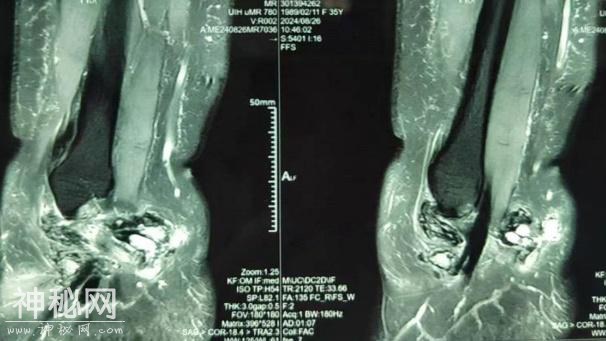

最近马女士觉得疼痛感愈发加重,来到市六医院金山分院诊治,接诊医生在为马女士做了MRI检查后发现,马女士的踝关节里居然有绒毛样的结节状阴影,结合问诊及检查报告等,考虑为左踝关节色素沉着绒毛结节性滑膜炎。

马女士的MRI检查

踝关节MRI上表现为踝关节内局灶性、结节样或弥漫性增生的滑膜,一般无钙化,可呈均匀高密度影,也可有关节囊积液。

病变进一步发展会出现骨质侵蚀,表现为踝关节非负重区有多发囊性病灶,边缘清晰,有薄的硬化边,晚期关节间隙进行性变窄,一般无骨赘形成。